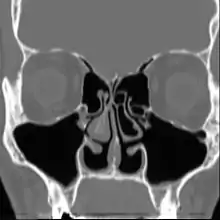

| Altered nasal anatomy after bilateral subtotal inferior turbinectomy, the removal of most turbinate tissue. | |

Empty nose syndrome (ENS) is a clinical syndrome, the hallmark symptom of which is a sensation of suffocation despite a clear airway. This syndrome is often referred to as a form of secondary atrophic rhinitis. ENS is a potential complication of nasal turbinate surgery or injury.[1][2] Patients have usually undergone a turbinectomy (removal or reduction of structures inside the nose called turbinates) or other surgical procedures that injure the nasal turbinates.

The condition is caused by injury to the nasal turbinates, particularly with nasal procedures. This includes both minor procedures as well as total turbinate resection. It is usually observed in patients with unobstructed nasal passages following surgical intervention who report sensations of suffocation or obstruction following recovery. Early literature attributed ENS to complete turbinate resection, but later research demonstrated the syndrome in patients who had undergone a range of procedures that involved nasal turbinates.[3][5][6][7][8]